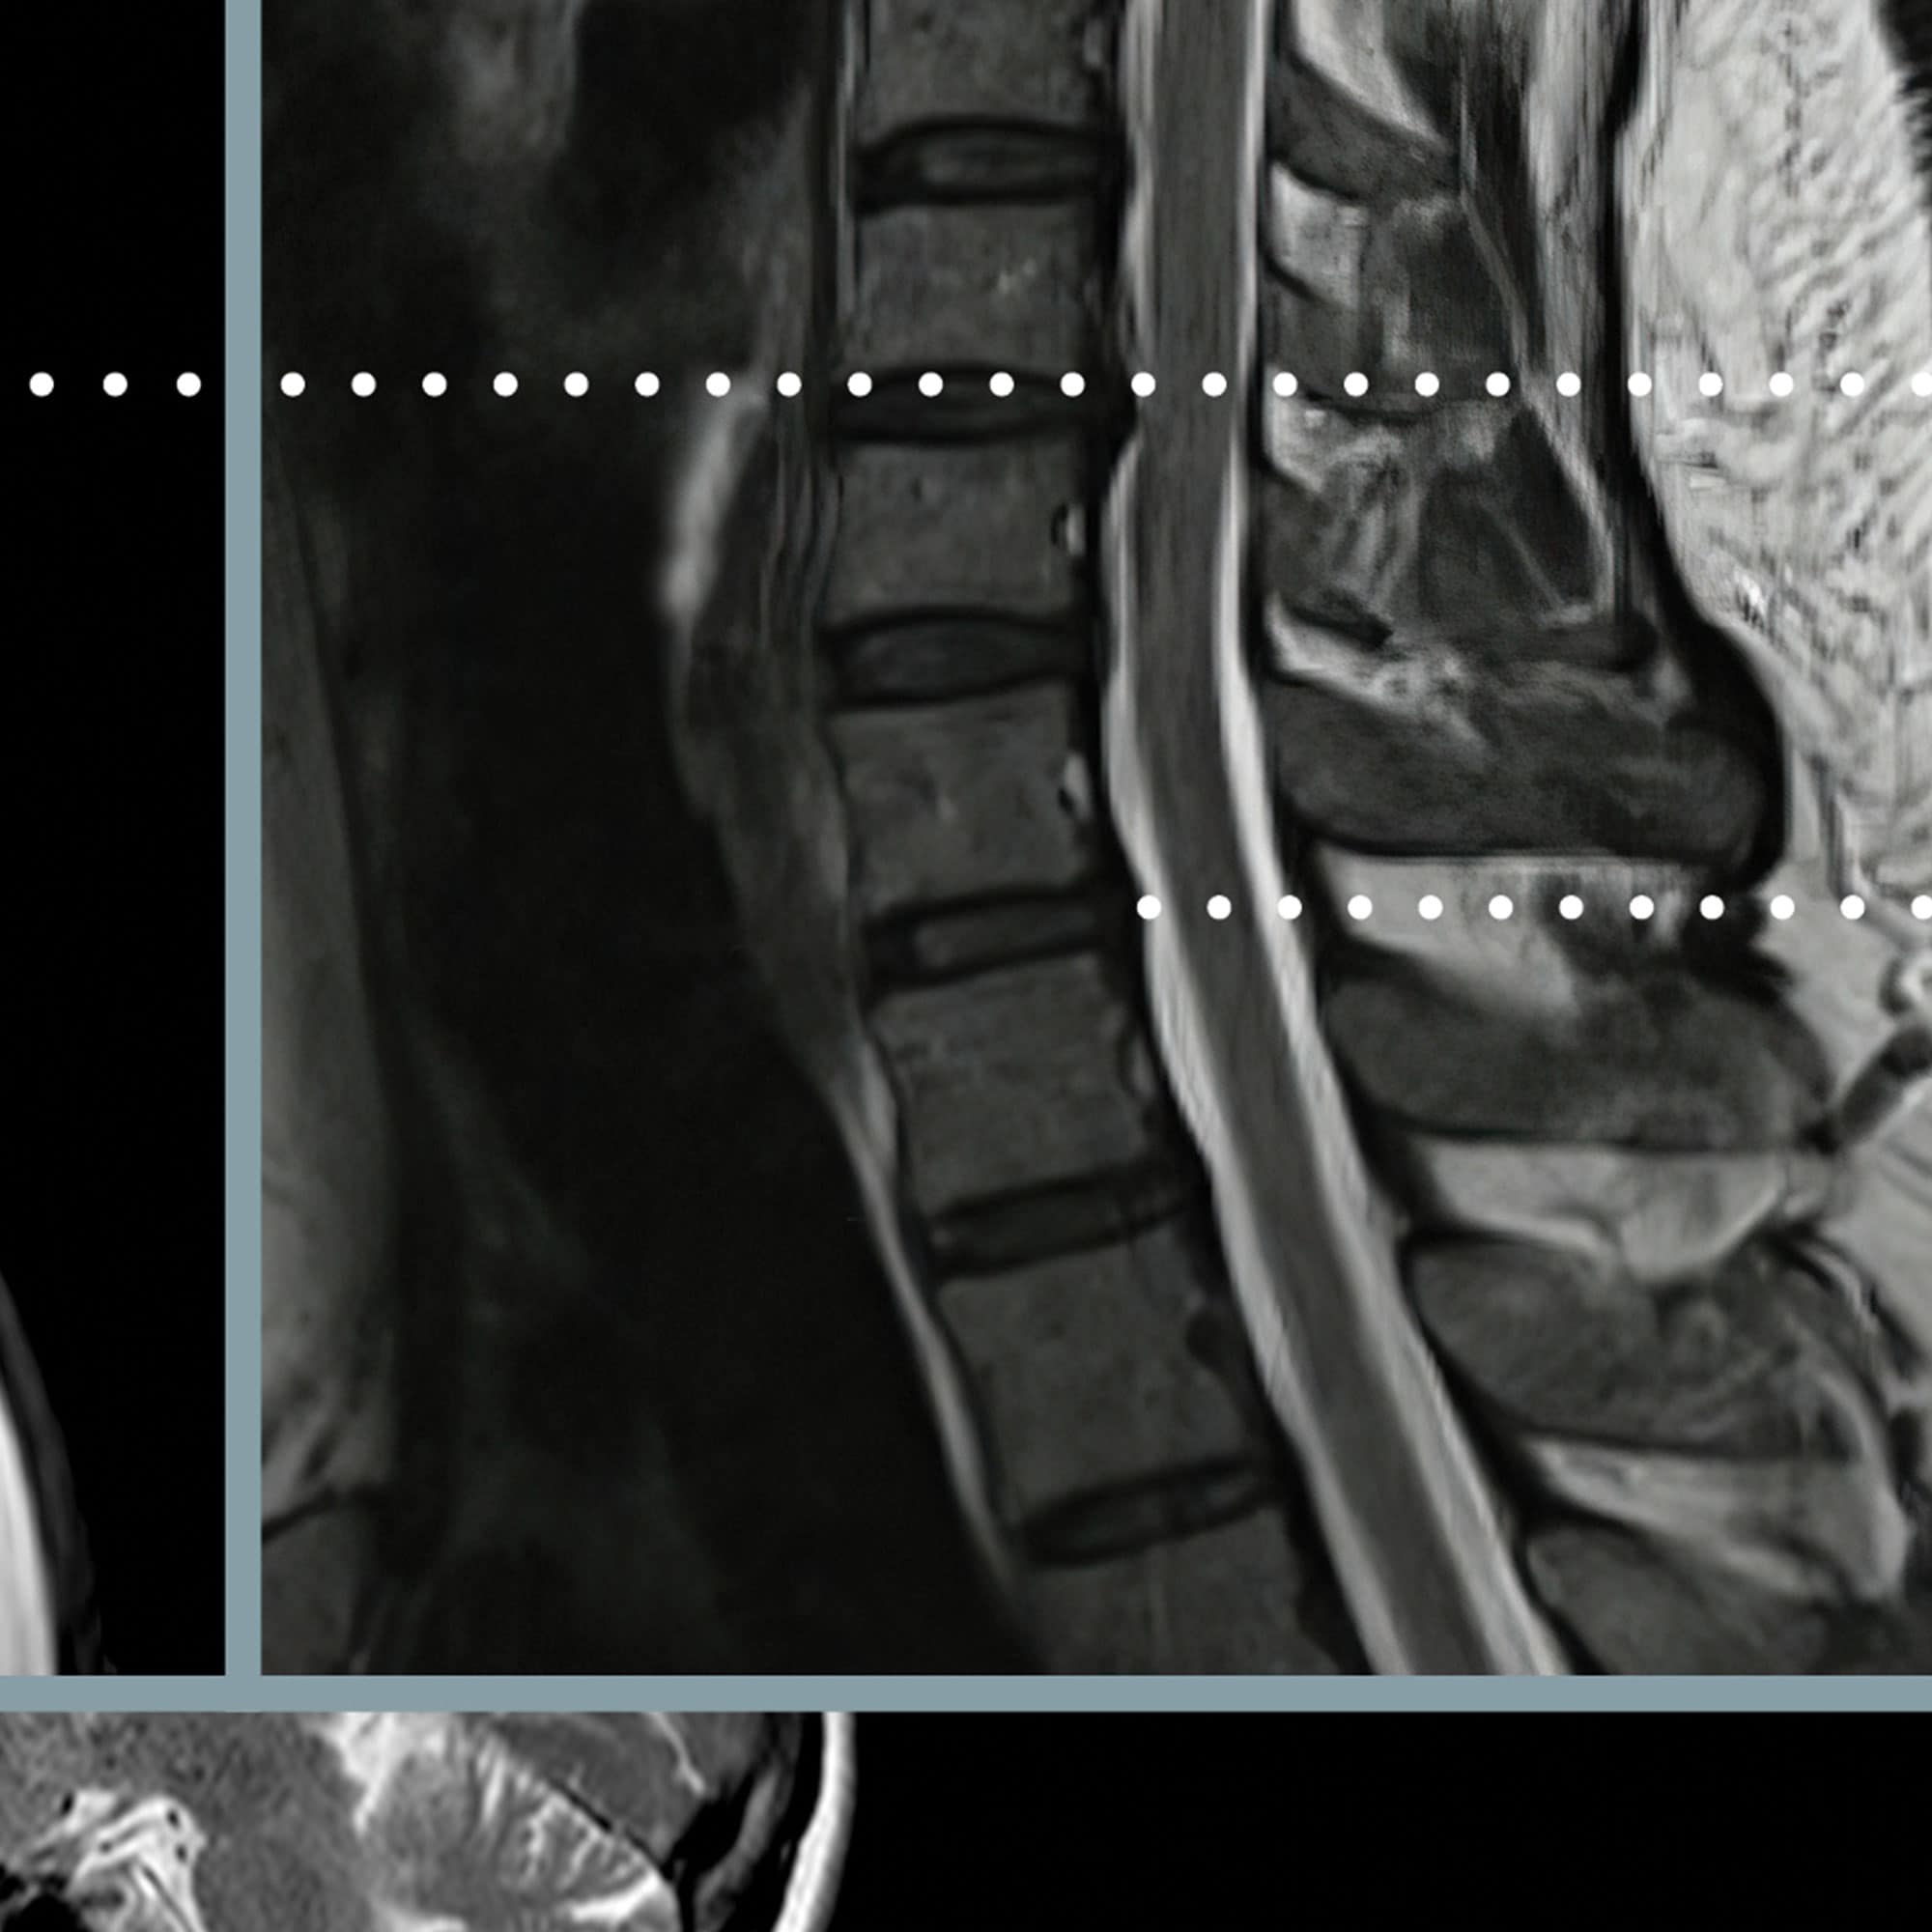

Cervical Pathology

Educating individuals about cervical pathology is crucial in raising awareness about the condition, its causes, and preventive measures. This can include sharing information on maintaining good posture, regular exercise, avoiding excessive strain on the neck, and seeking medical attention if symptoms persist. This artwork immediately improves comprehension by adhering to the belief that seeing is believing!